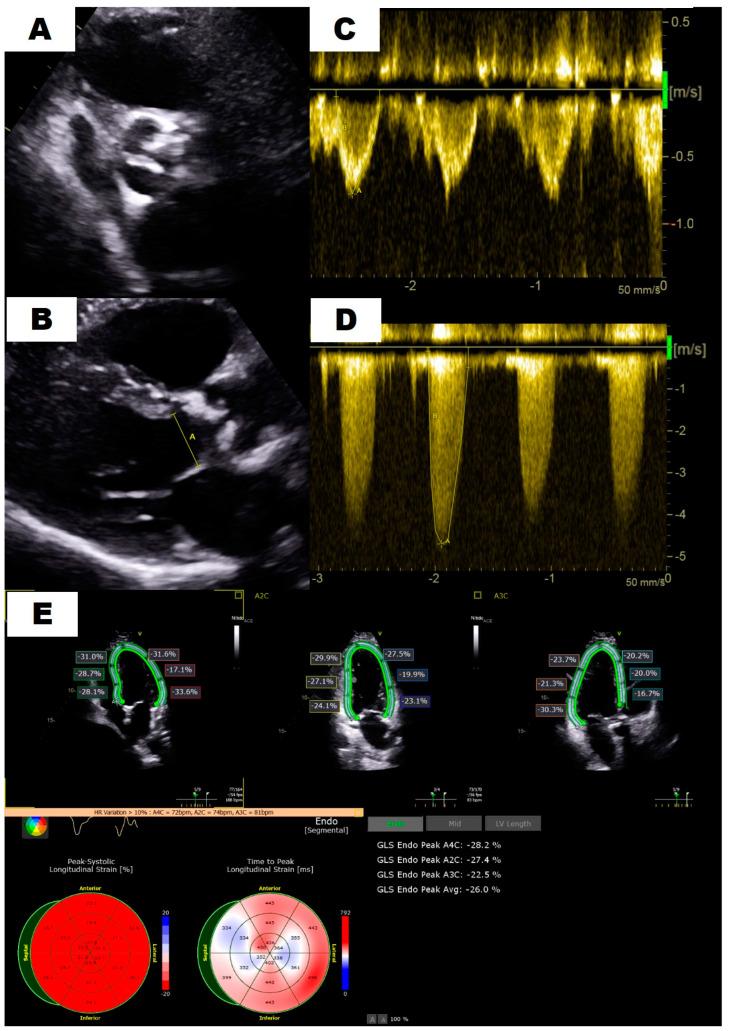

: Severe aortic stenosis (AS) may present with different flow, gradient and left ventricular ejection fraction (LVEF) patterns. Paradoxical low-flow low-gradient (PLF-LG) severe AS has a specific clinical profile, but its prognosis and management remain controversial. Our aim is to evaluate the impact of different AS patterns in the incidence of major clinical events. : A retrospective observational study was carried out on all the consecutive patients diagnosed with severe AS at our tertiary hospital centre in 2021. Echocardiographic measurements were carefully reviewed, and patients were classified following current guidelines into four categories: high gradient (HG), concordant low-flow low-gradient (CLF-LG), paradoxical low-flow low-gradient (PLF-LG) and normal-flow low-gradient (NF-LG). The baseline characteristics and clinical events (heart failure admission, intervention and death) at 1-year follow-up were collected from medical records. The association between categories and events was established using Student's test or ANOVA as required. : 205 patients with severe AS were included in the study (81 ± 10 years old, 52.7% female). Category distribution was as follows: HG (138, 67.3%), PLF-LG (34, 19.8%), CLF-LG (21, 10.2%) and NF-LG (12, 5.9%). During the follow-up, 24.8% were admitted due to heart failure, 68.3% received valve replacement (51.7% TAVR) and 22% died. Severe tricuspid regurgitation was more frequent in patients with PLF-LG than in HG AS (14.7% vs. 2.2%; < 0.01). Despite no differences in intervention rate, more patients with PLF-LG (32.4% vs. 15.9%; = 0.049) died during the evolution. : The PLF-LG pattern was the second most common pattern of severe AS in our cohort, and it was related to a higher mortality with no differences in intervention rate. Thus, this controversial category, rather than being underestimated, should be followed closely and considered for early intervention.

重度主动脉瓣狭窄(AS)可能呈现不同的血流、压力阶差和左心室射血分数(LVEF)模式。矛盾性低流量低压力阶差(PLF-LG)重度AS具有特定的临床特征,但其预后和治疗仍存在争议。我们的目的是评估不同AS模式对主要临床事件发生率的影响。:对2021年在我们三级医院中心连续诊断为重度AS的所有患者进行了一项回顾性观察研究。仔细复查了超声心动图测量结果,并根据现行指南将患者分为四类:高压力阶差(HG)、一致性低流量低压力阶差(CLF-LG)、矛盾性低流量低压力阶差(PLF-LG)和正常流量低压力阶差(NF-LG)。从病历中收集了基线特征和1年随访时的临床事件(心力衰竭入院、干预和死亡)。根据需要使用学生t检验或方差分析确定类别与事件之间的关联。:205例重度AS患者纳入研究(年龄81±10岁,女性占52.7%)。类别分布如下:HG(138例,67.3%)、PLF-LG(34例,19.8%)、CLF-LG(21例,10.2%)和NF-LG(12例,5.9%)。随访期间,24.8%因心力衰竭入院,68.3%接受了瓣膜置换(经导管主动脉瓣置换术占51.7%),22%死亡。PLF-LG患者中重度三尖瓣反流比HG AS患者更常见(14.7%对2.2%;P<0.01)。尽管干预率无差异,但在病程中PLF-LG患者死亡更多(32.4%对15.9%;P=0.049)。:PLF-LG模式是我们队列中重度AS的第二常见模式,它与较高的死亡率相关,干预率无差异。因此,这个有争议的类别不应被低估,而应密切随访并考虑早期干预。